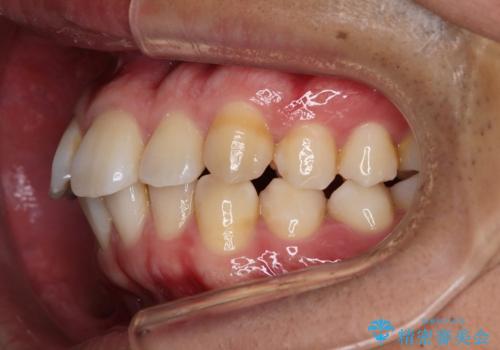

- 上の歯が出ているのが気になるのを主訴にご来院されました。人前で話すお仕事をされており目立たないマウスピース治療を希望されていました。

口元のEラインは気にならないとのことだったのでインビザラインにて治療していくことにしました。

IPR(歯と歯の間を削る処置)と歯列拡大をすることで前歯を少し下げ、がたつきを改善していく治療計画を立てました。

上の前歯が出ているという主訴が綺麗に改善されました。

その他の部位のがたつき、奥歯の噛み合わせも以前と比べると良くなっています。